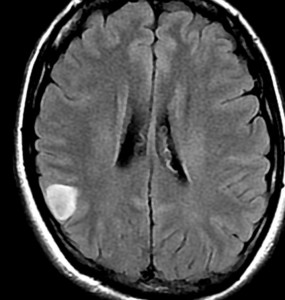

• MRI のT2・FLAIR(フレア)画像で淡く白く見える(高信号)のが特徴です

• 一般的には,びまん性で周囲がはっきりしない脳の中に「にじむような腫瘍」に見えます

• ガドリニウム造影剤で増強されることはほとんどありません

左側頭葉のびまん性星細胞腫です。左側のT1強調ガドリニウム像ではほとんど腫瘍は見えません。真ん中のT2強調画像でも見づらいです。右側のフレア画像で白くにじんでいるところに腫瘍があります。どこまでが腫瘍の境界なのかがはっきりしない腫瘍です。左の海馬(記憶の中枢)を侵し,とてもゆっくり大きくなるタイプで,この患者さんは10年以上治療をしないで経過を見ています。全摘出できない星細胞腫グレード2です。